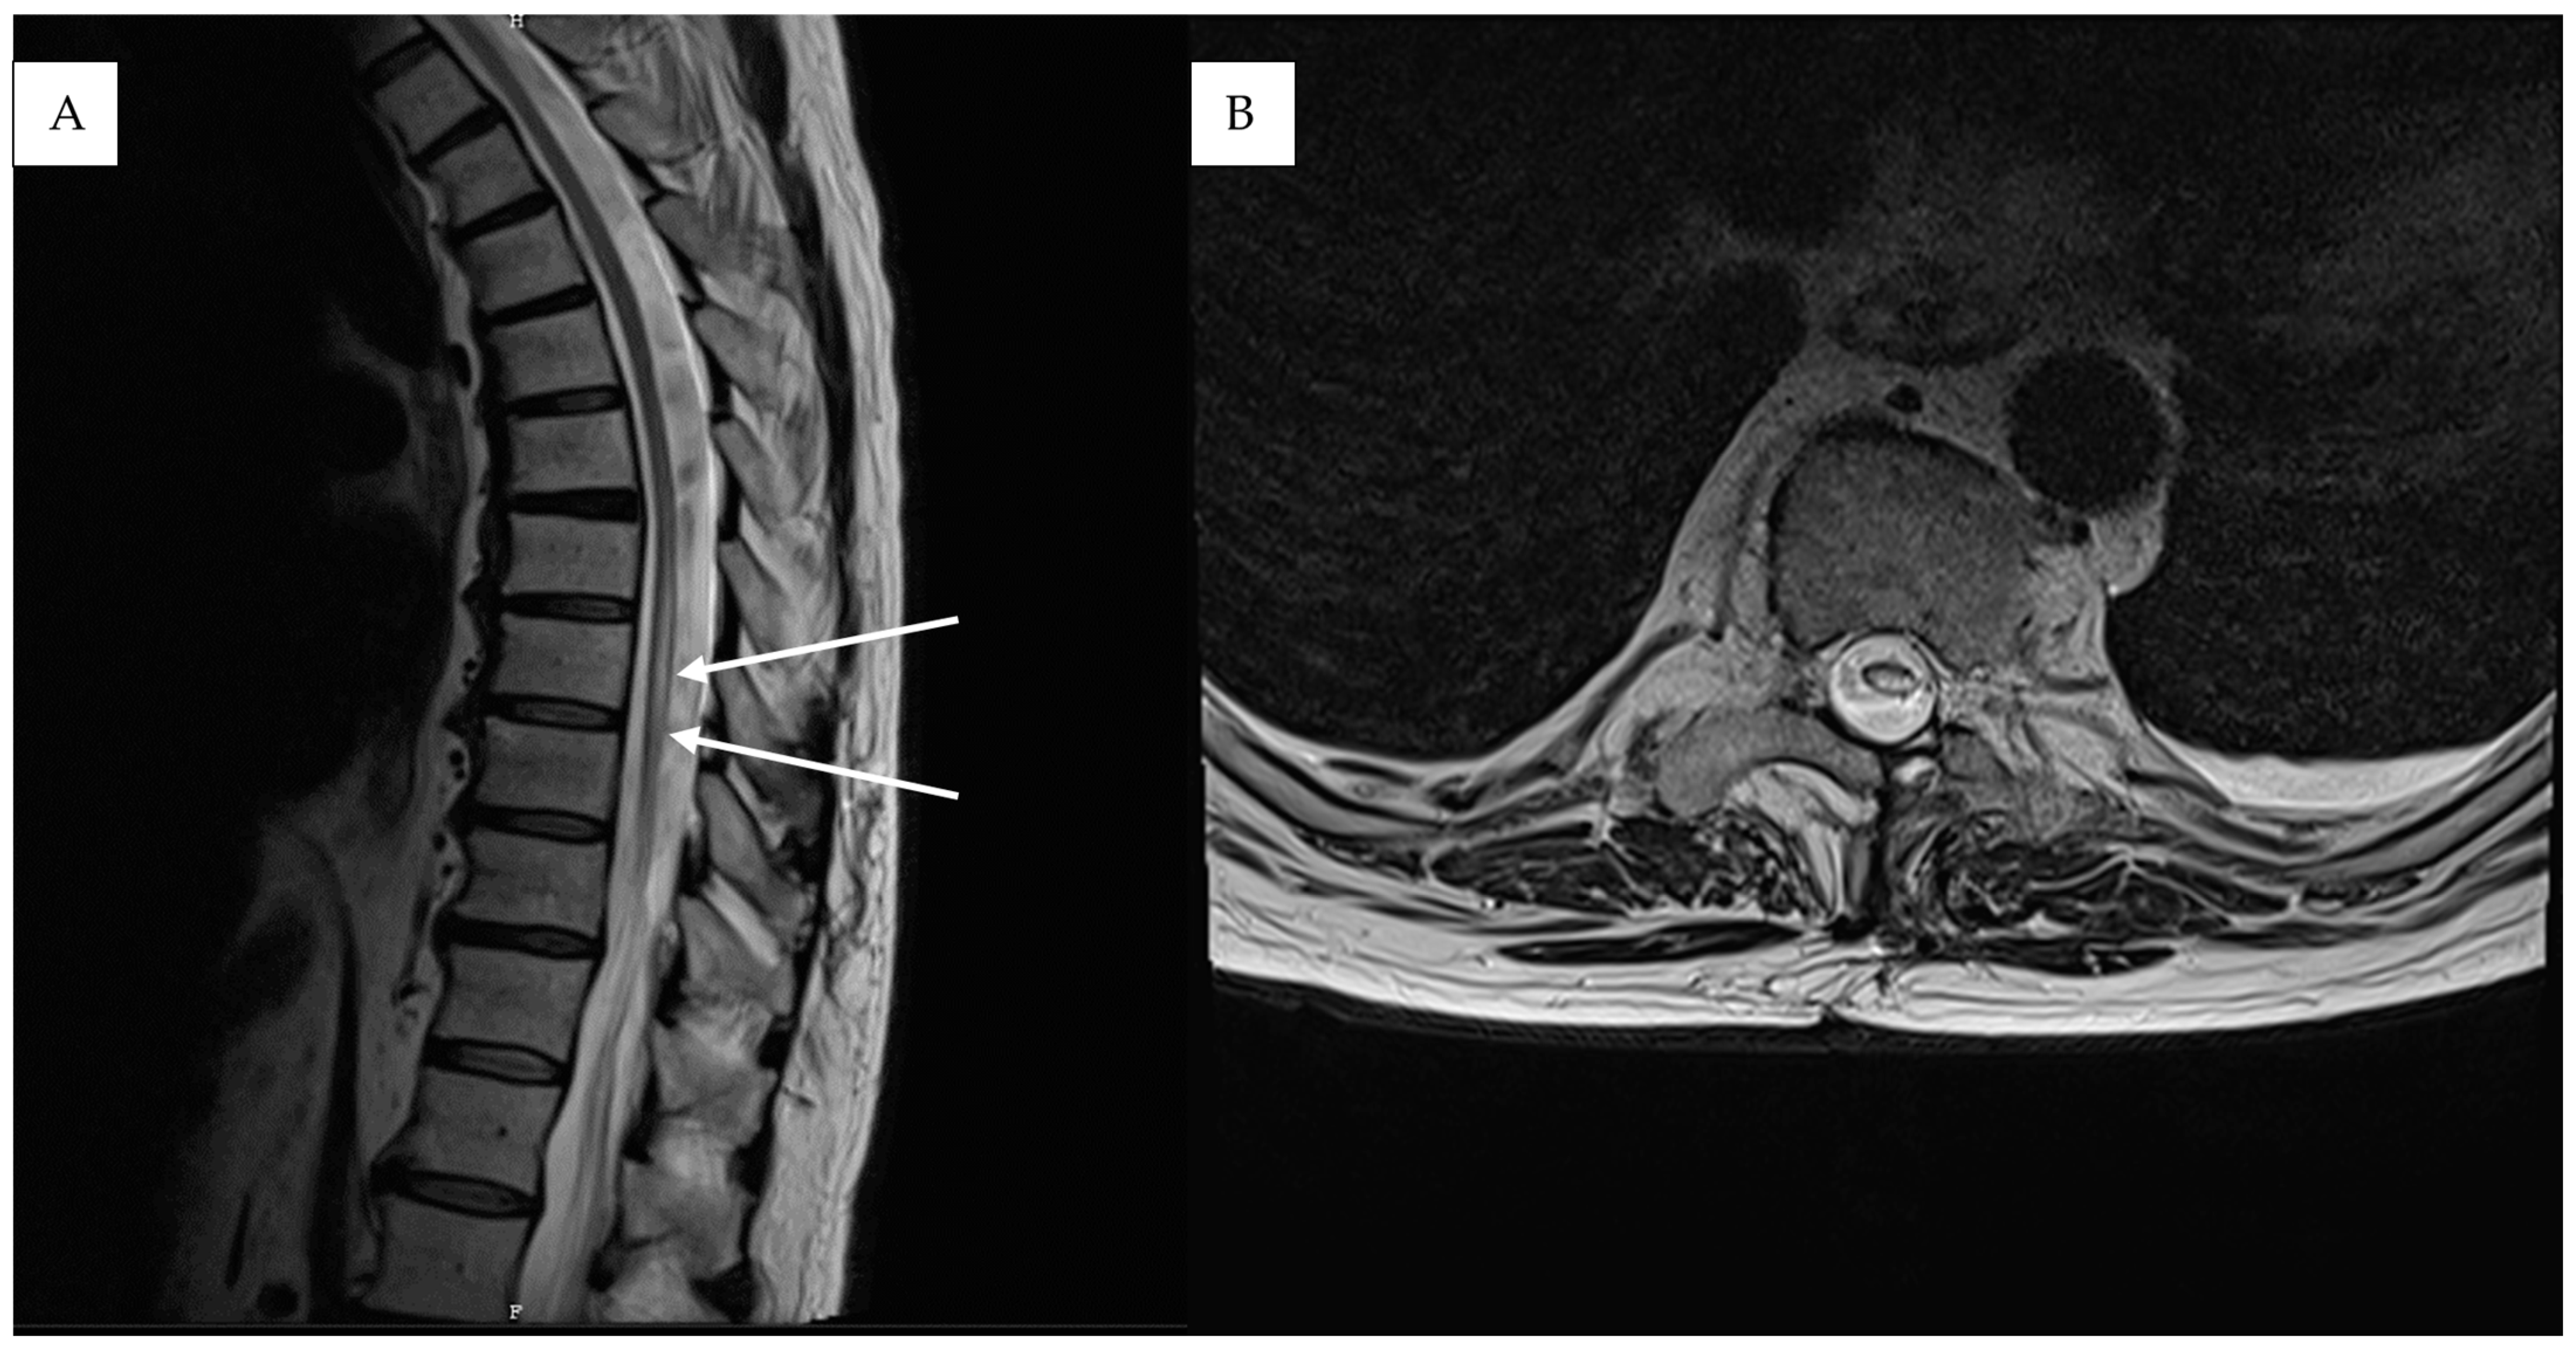

2. Detailed Case Description